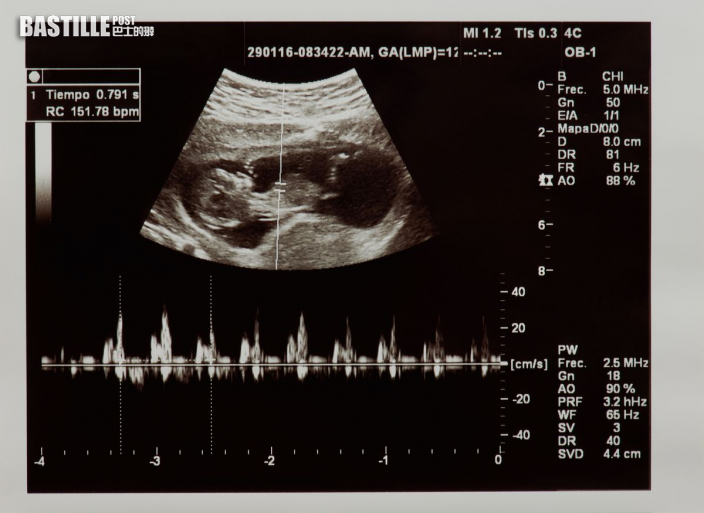

坊間有不少避孕方法,但沒有一個有百分百的安全保證。台灣一名婦產科醫生在一個節目上分享,指一名42歲的太太裝避孕器10年也「中招」,胎兒被發現時已有20周大。經調查後發現,原來避孕器是被寶寶用腳踢走,並卡在媽媽的子宮頸跟子宮下段。

據該醫生引述,該名太太因下體有異常出血和肚子痛,感到困擾而求診。醫生為她進行超聲波檢查時一看,竟發現其腹內有胎兒,遂立即跟對方說:「恭喜,你42歲還懷孕了這樣子。」